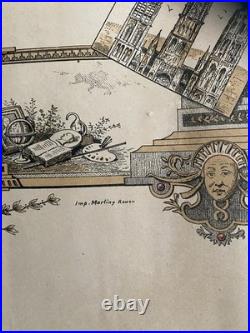

Ecole de Pharmacie de Paris (1836) : Diplôme de pharmacien 1836. La création et l’organisation de l’Ecole de Pharmacie de Paris datent de la loi du 11 avril 1803 et du décret du 8 octobre de la même année. De sa création en 1803. À son rattachement à l’Université en 1840, aucun acte législatif ou règlementaire majeur ne vient modifier la situation de l’école. En 1803 comme en 1836, date de ce document, des professeurs de l’Ecole de Médecine de Paris siègent dans les jurys d’examen. Ceci explique que ce diplôme soit délivré par les «. Professeurs à l’Ecole de Pharmacie de Paris, et Professeurs à l’école de médecine de la même Ville. Pour l’Ecole de Médecine. Médecin et chimiste espagnol, naturalisé français en 1818, il est un pionnier de la toxicologie médico-légale. Il signe ce document deux fois. La première en qualité de professeur, depuis 1819, à la faculté de médecine de Paris. La seconde comme doyen (1831 à 1848) de cette même école. Depuis 1834, il est également membre du Conseil royal de l’Instruction publique. Reçu docteur en médecine en 1820, il devint aide naturaliste au Muséum d’Histoire naturelle en 1827. En 1831, il obtient la place de professeur d’histoire naturelle médicale à la Faculté de Médecine de Paris, reprenant ainsi la fonction de son père, le botaniste Louis Claude Richard (1754 -1821). Pour l’Ecole de Pharmacie. Reçu maître en pharmacie en 1787, il s’adonne ensuite à la chimie. Attaché comme pharmacien à la maison de l’empereur, il accompagne Napoléon Ier lors de ses campagnes en Autriche et en Prusse. Lors de la fondation en 1803 de l’école de pharmacie, il occupe la chaire de chimie. En 1829, il devint directeur-adjoint et en 1832 directeur. C’est à ce poste qu’il signe ce diplôme. Pharmacien et chimiste français. Il fait d’importantes recherches sur les alcaloïdes d’origine végétale et découvre avec Joseph Caventou la quinine et la strychnine. Figure éminente de la pharmacie et de la chimie, ses recherches mettent en évidence plusieurs principes actifs comme la caféine, la narcotine et surtout la codéine. Louis René Le Canu. Il fait notamment paraître plusieurs mémoire sur le sang, sujet qui ne cesse de l’occuper pendant toute la durée de sa carrière. Document su vélin (335 x 216) avec frontispice au coq et « caducée exotique ». Diplôme délivré à Paris le 2 février 1836 et attribué à Joseph Alexandre BLANCHART. Ce dernier, né en 1812 à Péruwelz en BELGIQUE d’un père pharmacien, bénéficie d’une dispense d’âge pour ses examens. Diplôme avec un pli dans le sens de la longueur et trois dans la largeur. Les produits proposés à la vente sont de nature, de poids et de tailles très hétérogènes. Le paiement est considéré comme « soldé » une fois que l’argent envoyé par l’acheteur a été déposé sur le compte du vendeur. Paiement en ligne par carte bancaire. Par virement national ou international.